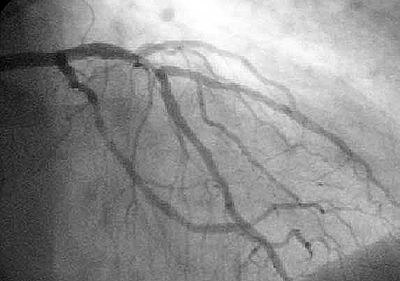

• Angiografía

Angiografía

El portugués Egas Moniz fue el primero en el desarrolló la angiografía por contraste como diagnóstico de trastorno celebral. Produciendo imágenes detalladas de los vasos sanguíneos,

• Primer Algoritmo de IA usando MRI

FDA aprueba primer algoritmo de Inteligencia Artificial (AI) en imágenes cardiacas usando MRI.